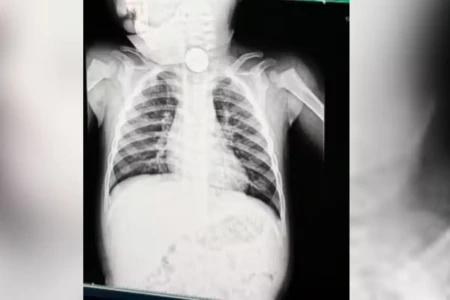

Exame revelou bateria do brinquedo lousa mágica no esôfago do bebê (Foto: redes sociais)

Bateria de brinquedo faz bebê de 1 ano ir parar no hospital com início de necrose em Goiânia

Criança de 1 ano engoliu bateria de lousa infantil, ficou 12 horas com o objeto no esôfago e teve que passar por endoscopia para retirar